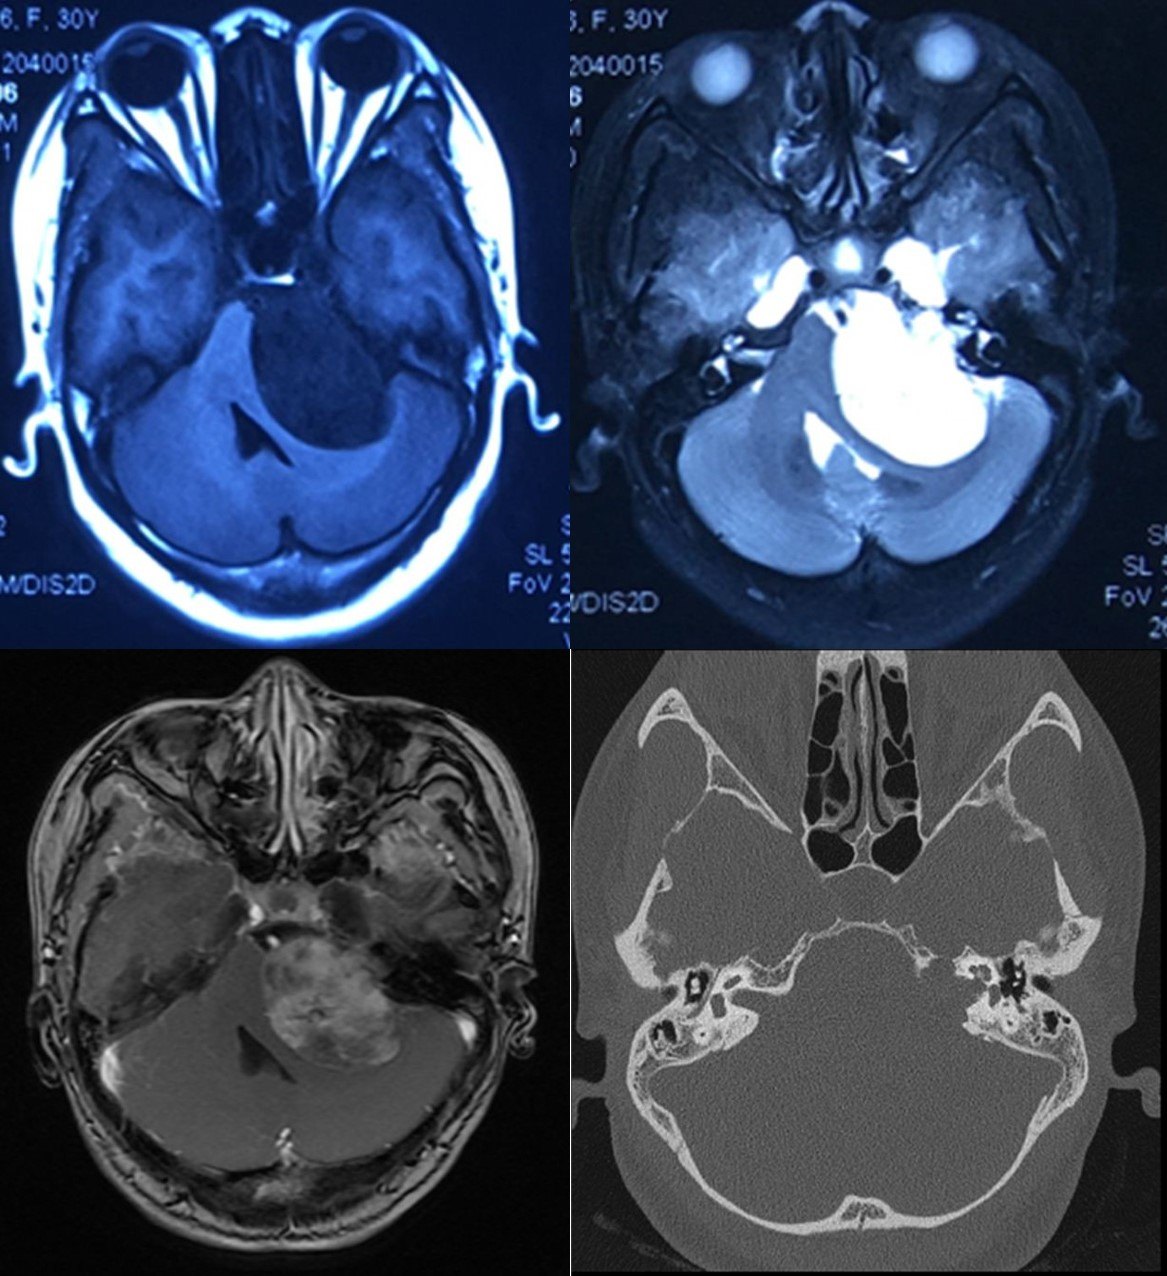

病例:女,30岁,因眩晕、进食呛咳伴一侧听力进行性下降入院。

头颅MRI示:左侧桥脑小脑角占位性病变,短T1长T2,不均匀强化,脑干、小脑及四脑室受压明显。CT显示左侧内听道扩大。